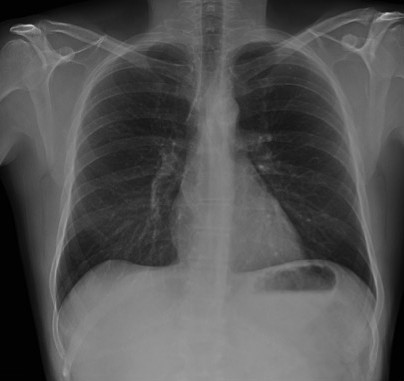

CASO: Febrícula y tos de 4 días de evolución.

Hallazgos:

- En la placa PA se observa una asimetría en los hilios pulmonares, el hilio izquierdo tiene una densidad aumentada.

- Tras examinar la placa lateral se observa un aumento de densidad en la columna que puede ser compatible con una condensación, es el signo de la desnificación vertebral.

SIGNO DE LA DENSIFICACIÓN VERTEBRAL: En la radiografía lateral normal, la densidad de la columna torácica tiende a disminuir desde la parte superior hasta el diafragma; la alteración de ese patrón por la presencia de una densidad superpuesta a la columna, indica la existencia de una consolidación pulmonar. Este signo adquiere especial valor cuando en la proyección posteroanterior la consolidación está oculta en el espacio retrocardíaco o en la base pulmonar.